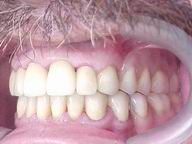

Reabilitação funcional e estética em ambas as arcadas

com próteses fixas e removíveis de encaixe de precisão.

DEPOIS

Vista Lateral Esquerda